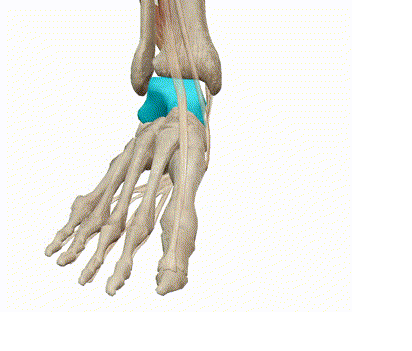

7、跗跖关节复合体(Lisfranc 关节复合体)损伤

与跗跖关节韧带相关的骨折常由旋前或旋后的跖屈损伤引起。尽管跗跖关节骨折脱位仅占所有骨折的 0.2%,但是约 20% 的这些骨折在初次检查时被漏诊。初次X片可能示正常,但是负重位X线片常常提示脱位或半脱位。

典型表现:第二跖骨底和内侧楔骨之间的骨折碎片,跖骨间间隙增宽,脱位亦可发生在舟骨-内侧楔骨关节,导致另一种变异的跗跖关节损伤(图A)。此外,骰骨的小块皮质撕脱在足部斜位片上可清晰显示(图 B)。